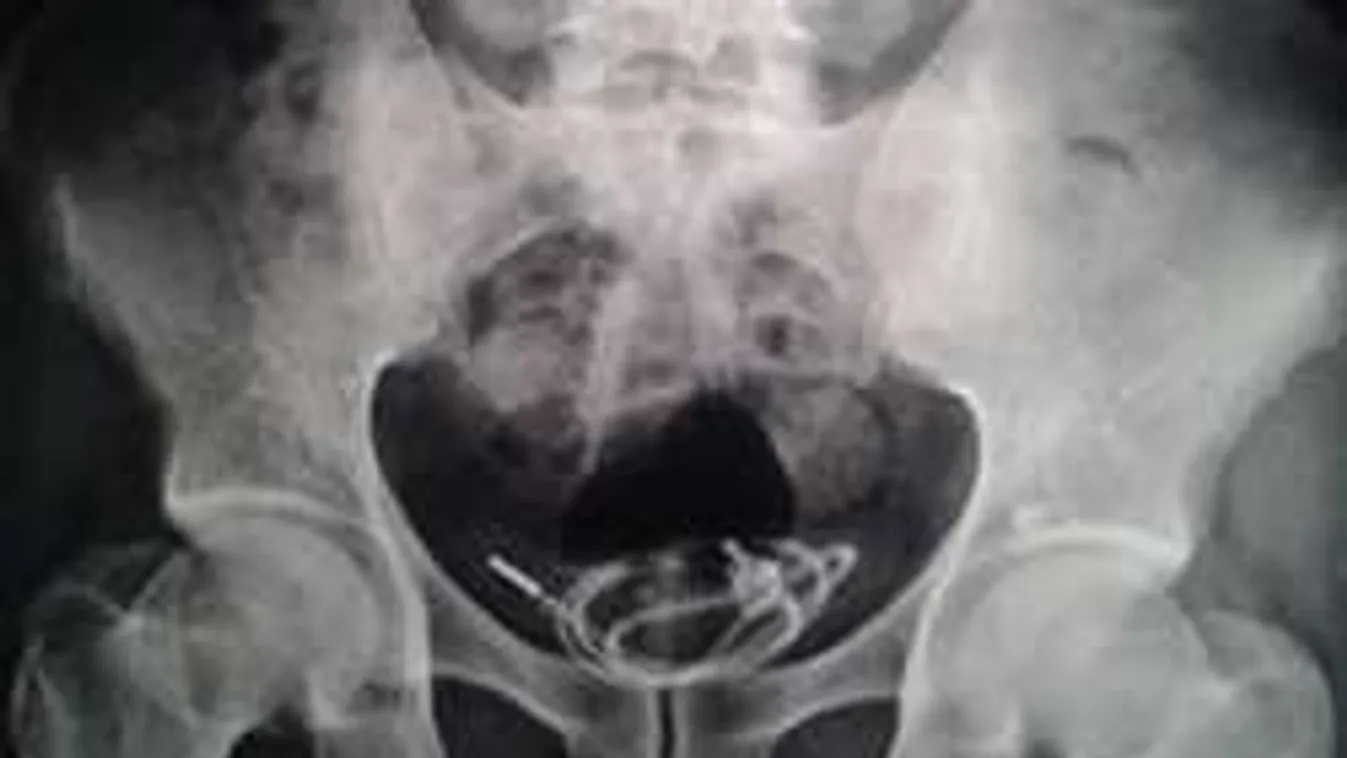

NA NE! 2018. 07. 06. Sokkot kapott az orvos, ezt találta a srác húgyhólyagjában Szegény fiú túl kíváncsi volt, amikor bizarr módon kényeztetni szerette volna magát. Nagyon rossz vége lett...

BIZARR 2016. 10. 26. Sokkot kaptak az orvosok, amikor rendelőbe került a maszturbáló férfi Szex-balesetek mindig is voltak. Lassan nincs olyan morbid történet, amin fennakadnánk. A következő sztori azonban nálad is biztosan kiveri a biztosítékot.